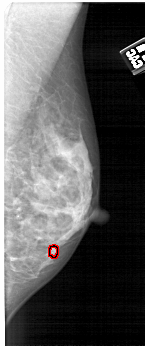

FILE: A_1497_1.RIGHT_CC.OVERLAY

TOTAL_ABNORMALITIES 1

ABNORMALITY 1

LESION_TYPE CALCIFICATION TYPE PLEOMORPHIC DISTRIBUTION CLUSTERED

ASSESSMENT 4

SUBTLETY 2

PATHOLOGY BENIGN

TOTAL_OUTLINES 1

BOUNDARY